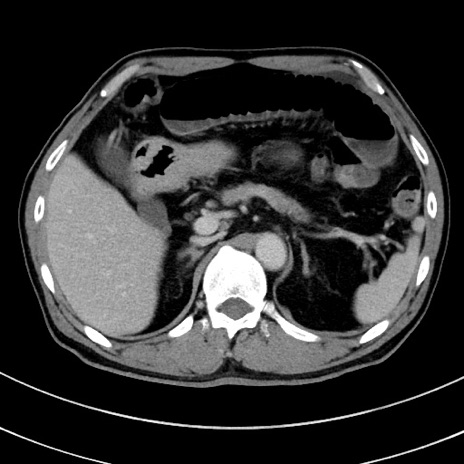

症例8(横断像)

【症例】 60歳代男性

【主訴】 黒色吐物

【現病歴】 4日前から嘔気自覚、2日前の朝食後にも嘔気あり、自分で手で嘔吐反射起こし嘔吐したところ血が混ざっていたため受診。

【既往歴】 5年前汎発性腹膜炎を伴う急性虫垂炎で手術、高血圧、前立腺肥大症、高脂血症

【身体所見】 腹部正中に手術癩痕あり 腹部平坦・軟圧痛なし膨満感あり

【データ】WBC 8400、CRP 4.54